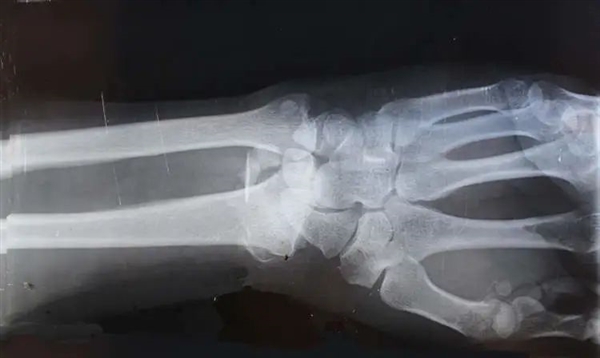

1994年,約翰發(fā)生了車禍,現(xiàn)場(chǎng)非常慘烈,足以讓一個(gè)普通人骨頭碎裂的程度。

約翰被送到了醫(yī)院,照了X光,結(jié)果醫(yī)生驚奇地發(fā)現(xiàn),約翰全身上下,找不到一處骨折的地方。

正當(dāng)大家還在疑惑的時(shí)候,醫(yī)生還發(fā)現(xiàn),約翰的骨密度異常高,是正常人骨密度的8倍。

骨密度,是指單位體積的骨頭里骨礦物質(zhì)的質(zhì)量,是判斷骨骼是否健康的一個(gè)指標(biāo),一個(gè)成年男性骨密度值大約為1.228g/cm3。

骨密度的8倍,可想而知,這個(gè)人的骨頭是多么地致密和堅(jiān)硬了。